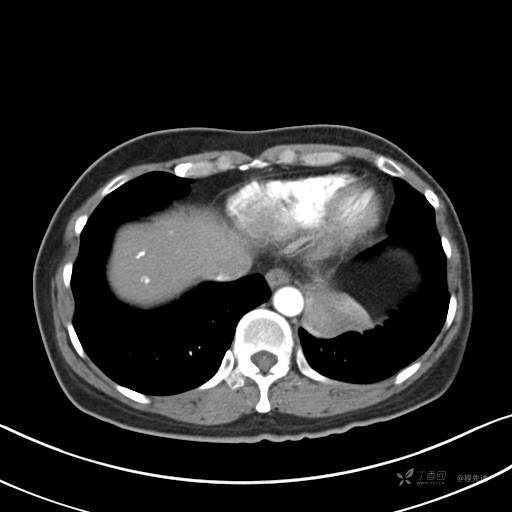

冠状位重建

CT值:平扫:31HU,动脉期:74HU,静脉期:84HU